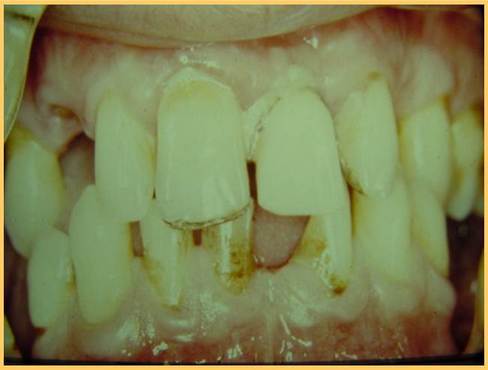

下のリーゲルテレスコープの途中経過。

そして、完成です。

ドイツで、35年前、Körber教授の指導の下、初めてのリーゲルテレスコープ症例を 行った私の思い出の症例です。